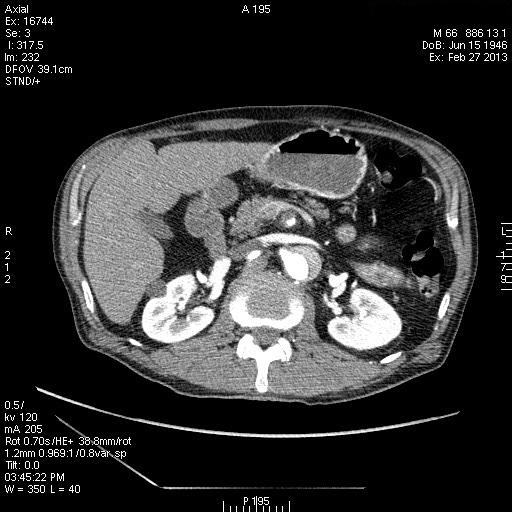

Расслаивающая аневризма аорты, Дебейки I

Пожилой пациент с жалобами на боли в грудной клетке. Болеет неделю.

Диссекция аорты

Диссекция аорты 1 типа по DeBakey , Стенфорд А .